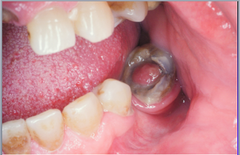

Inflamed pulp tissue within a tooth that is severely decayed or has a large open caries lesion a)gingival hyperplasia b)papillary hyperplasia of the palate c)epulis fissuratum d)chronic hyperplastic pulpitis-pulp polyp

Front

Chronic Hyperplastic Pulpitis- pulp polyp

Back